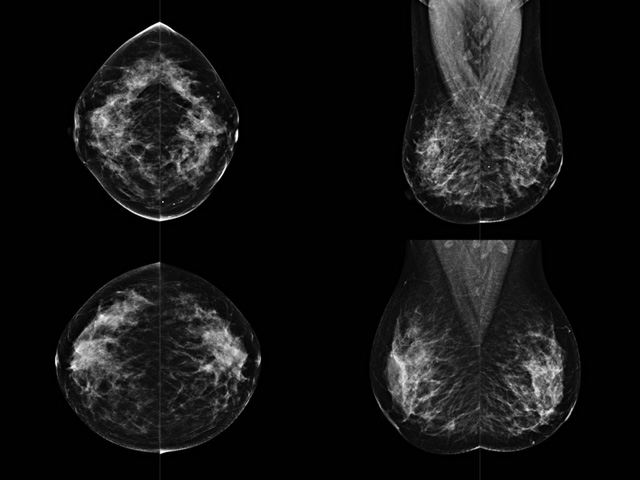

乳腺DR成像設備中非晶矽跟非晶硒兩種平板探測器。更要提供優質的圖像質量乳腺的組織結構與厚度各不相同,減少重拍率輻射劑量,,乳腺的主要構成組織均為軟組織結構,組織之間密度十分相似,缺乏天然對比度。選擇軟X線攝影技術獲得良好對比度的乳腺結構影像。增加各組織對X線的吸收差異。乳腺攝影測和分類,平板探測器的像素尺寸範圍應在50到100μm之間。特別是微鈣化灶可以小到100到200μm,平板探測器都必極小微鈣化灶進行成像。

乳腺DR是利用X光來做檢查,在一瞬間將被檢測到的位置投影出來,因為是瞬間的輻射,所以隻需要0.5秒的時間。因此對病人的輻射很低,大約是0.023mSv,比國家的標準要低得多。DR係統由 X線、發生裝置、直接轉換平板探測器、係統控製器、影像監視器、影像處理工作站等組成。能檢查胸腔積液、肺結核、大葉性肺炎、肋骨骨折等。心室增大、主動脈擴張、主動脈瘤等心髒病。腹部病變,如腸梗阻、腸穿孔等,DR上可見液氣平麵、膈下遊離氣腫。DR表現不正常,要結合臨床表現、體征、症狀等綜合分析,結合CT、彩超、血液分析等,才能作出正確的判斷。